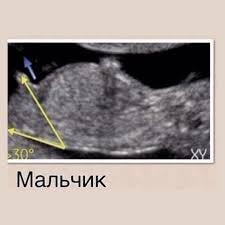

Согласна с комментарием ниже: на этом сроке пол если и можно увидеть, то с другого ракурса, сбоку. По углу наклона.

Gaechka, да, в этом ракурсе. Там так: если угол (от спинки, позвоночника) больше 30 градусов, то мальчик, если меньше, то девочка. Вот как на фотке.

Но это ж ещё чтоб малыш лег прям поровнее на спинку.